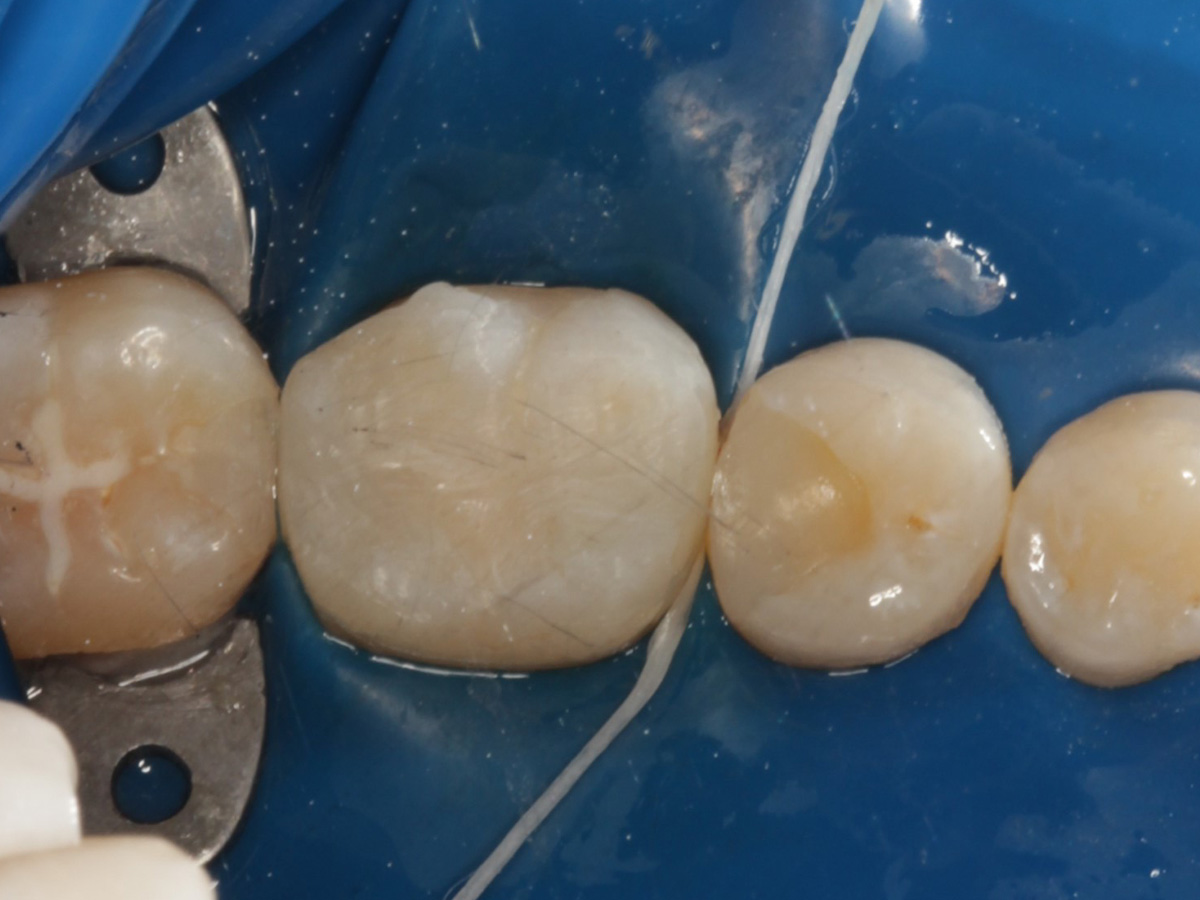

Kavitäten gefüllt (Injektion Moulding: Flowkomposit, erwärmtes Seitenzahnkomposit aus Karpule)

Abbildung 20

Abbildung 21

Zahnseidenkontrolle: kein Überschuss, satte Kontaktpunkte

Abbildung 22

Fertige Restauration Zahn 46